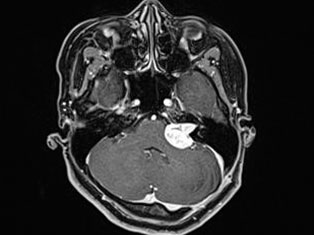

Brain Tumors

A brain tumor is a mass or growth of abnormal cells in your brain. Many different types of brain tumors exist. Some brain tumors are noncancerous (benign), and some brain tumors are cancerous (malignant).